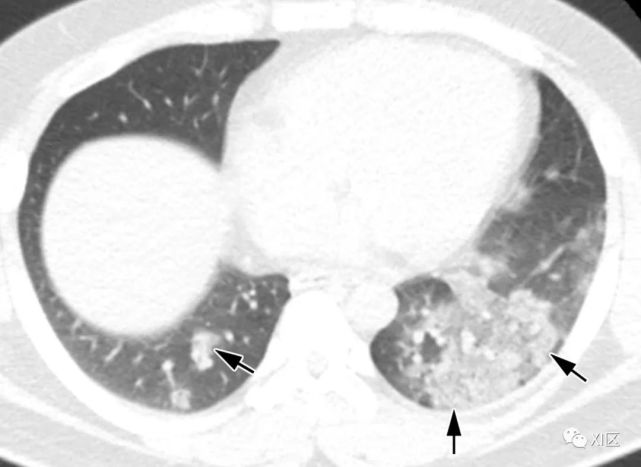

图片

图23 27岁男性,出现咳嗽和咳痰,诊断为MERS冠状病毒引起的肺炎。(上)最初的胸片显示,在下肺的两个区域,特别是在左心后区域,结节影(箭)区域增加。同一天在右下肺静脉水平(中上)以及右心房和下腔静脉交界处(中下)的冠状位重建图像(3mm) 椎体水平的图像(下)显示了两下肺叶的多发斑块状和结节样实变和GGO(箭头)。

Koo H J , Lim S , Choe J ,et al. Radiographic and CT Features of Viral Pneumonia[J]. Radiographics, 2018, 38(3):719-739.